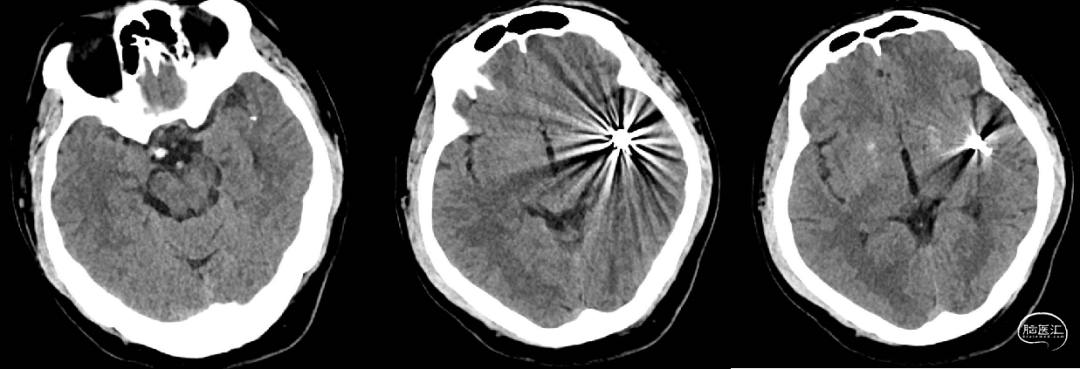

术后CT